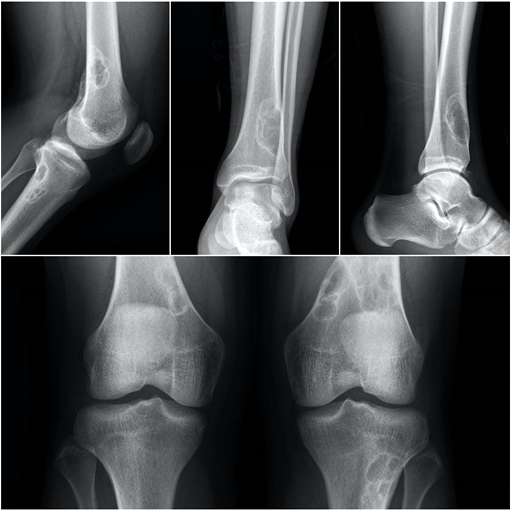

El fibroma no osificante o defecto fibroso cortical es la lesión benigna ósea que más frecuentemente encontraremos en los niños. Es una lesión particularmente asintomática detectada en su mayor parte de forma casual tras el estudio radiológico por otros motivos. Las características radiológicas muestran una lesión bien definida, excéntrica en la corteza del hueso, en ocasiones multilobulada y con bordes escleróticos. Puede existir adelgazamiento cortical aunque no hay reacción perióstica. Tiene predilección por las metáfisis de los huesos largos en los miembros inferiores.

El osteocondroma es la neoplasia más frecuentemente observada en el esqueleto. El osteocondroma es un tumor benigno que contiene hueso y cartílago. Forma unas excrecencias óseas recubiertas por cartílago en torno a las metáfisis de los huesos largos. Es muy frecuente en las zonas cercanas a la rodilla. También puede aparecer en el hombro y en los huesos del antebrazo. Es frecuente detectarlos en la adolescencia, pues la lesión puede provocar fenómenos inflamatorios con el roce sobre los tejidos blandos periarticulares, músculos o tendones. En caso de dolor y limitación se puede realizar cirugía, habitualmente con buenos resultados.

El encondroma es el tumor primario más frecuente en las manos, particularmente en las falanges proximales. También es frecuente en la tibia, en el tercio superior del fémur y en el húmero.En las radiografías solemos observar una lesión bien delimitada con matriz variable, desde osteolítica hasta intensamente mineralizada cuya imagen característica es de calcificaciones puntiformes, en grumos, anillos o arcos. En los huesos pequeños pueden ser muy expansivos, adelgazando la cortical del hueso, provocando dolor y fracturas patológicas. En huesos grandes no suele haber expansión del las corticales, pudiendo aumentar su tamaño intramedularmente y avanzar hacia la diáfisis.

El tumor de células gigantes es una lesión tumoral benigna pero localmente agresiva. Provoca lesiones líticas expansivas que se localizan fundamentalmente en las metáfisis y epífisis de huesos largos. La edad de aparición está entre los 20 y 50 años y se suele localizar con mayor frecuencia en la zona cercana a la rodilla, en la epífisis distal del fémur, en la tibia proximal y en el radio distal. Se describe la presencia de metástasis pulmonares en casi el 5% de los pacientes. Habitualmente el paciente refiere una historia de dolor persistente en torno a la rodilla, con afectación progresiva de la funcionalidad. Las fracturas patológicas suelen aparecer fundamentalmente en casos avanzados, con gran debilidad cortical. En la rodilla puede asociar derrame articular y fracturas osteocondrales por debilidad del hueso subcondral.